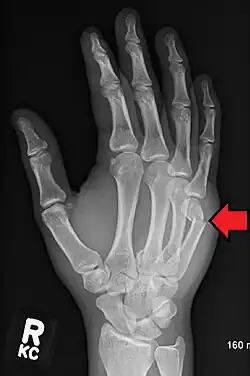

| Boxer's fracture of the 5th metacarpal head from punching a wall | |

Classically, it occurs after a person hits an object with a closed fist.[3] The knuckle is then bent towards the palm of the hand.[3] Diagnosis is generally suspected based on symptoms and confirmed with X-rays.[3]

Diagnosis by a doctor's examination is the most common, often confirmed by x-rays. X-ray is used to display the fracture and the angulations of the fracture. A CT scan may be done in very rare cases to provide a more detailed picture.